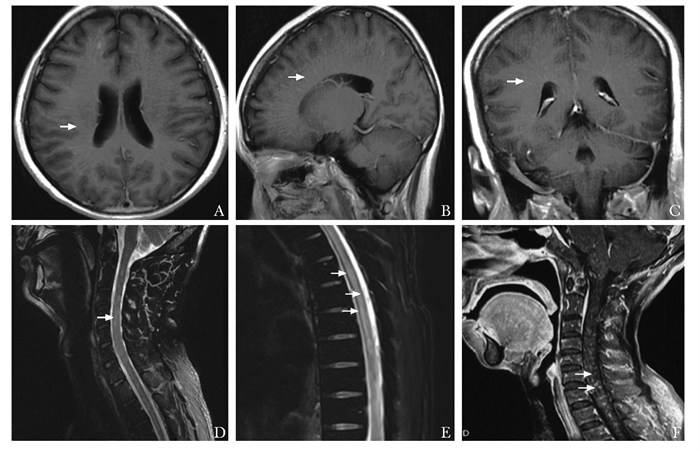

齿状核红核苍白球路易体萎缩症一例

罗赛, 江泓

2022, 1(2): 183-188. DOI: 10.12376/j.issn.2097-0501.2022.02.012

摘要 HTML全文 PDF